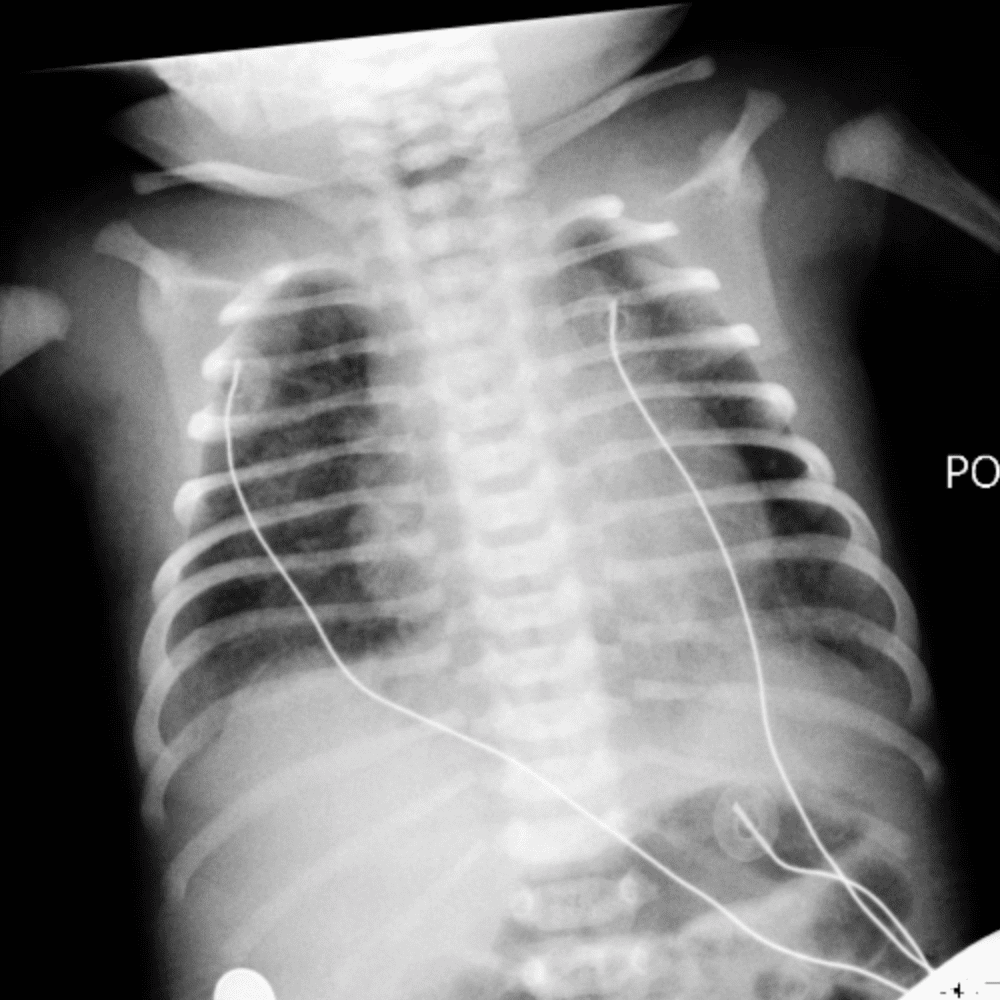

Peds Chest

Practice

Simulates call by including subtle or difficult cases and some normals.

50 cases